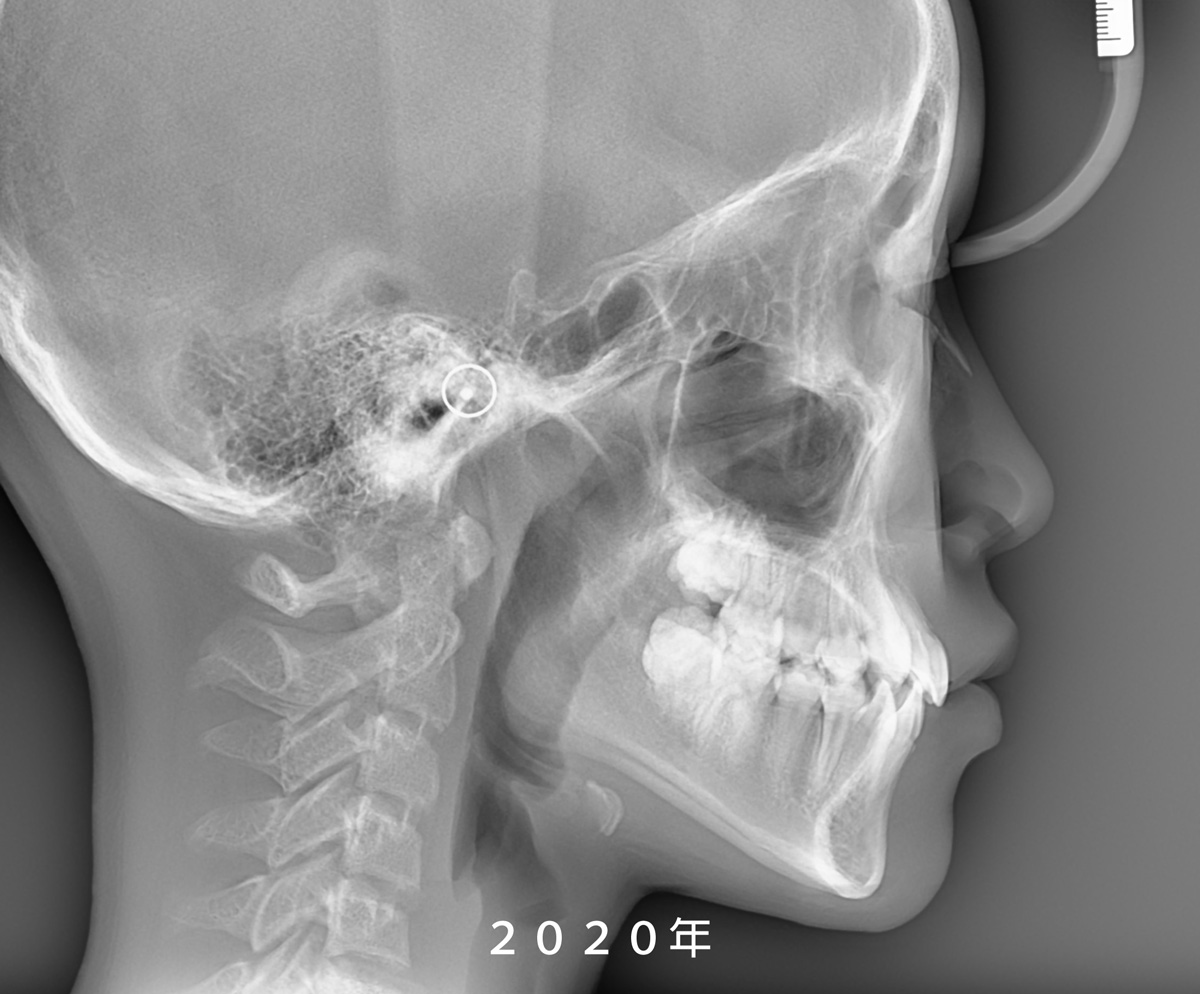

從 X 光片重疊影像可以發現,

她的鼻子與下巴都有明顯的成長變化,

但所幸前牙並未發展成

我們較為擔心的反咬(negative overjet)問題。

Because the pandemic reduced Yun’s visit frequency for nearly two years, it unexpectedly gave us a clearer window into her jaw growth. Superimposed X-rays showed noticeable changes in both her nose and chin, but thankfully her front teeth never shifted into a negative overjet, which is a common concern in skeletal Class III cases.